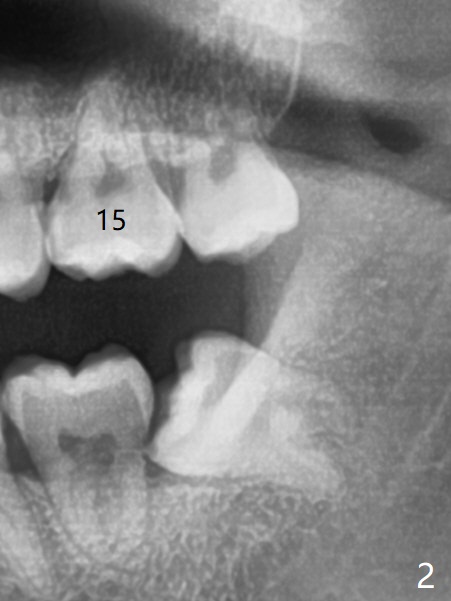

A 19-year-old man with mental retardation returns to clinic for extraction of the 3rd molars in 2 visits (Fig.1,2). The sockets heal without delay (Fig.3,4).